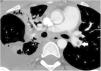

Buena evolución clínica con disminución de las necesidades de oxígeno, pero en la tomografía computarizada (TC) torácica realizada para valorar el derrame pleural se describe TEP en la arteria pulmonar izquierda (fig. 1). Por la ausencia de repercusión clínica se aumenta la dosis de enoxaparina a dosis de tratamiento (1mg/kg/12h para mantener antifactor-Xa entre 0,3-1U/ml) durante 3 meses, tras los cuales se objetiva resolución en la TC de control.